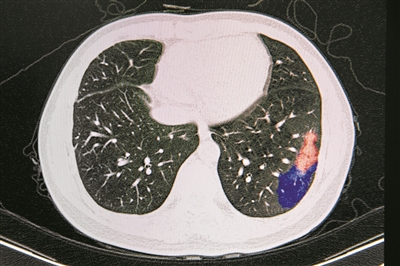

廣州三大科技戰“疫”成果亮相發布會 AI輔助診斷水平 相當于副教授

昨日下午,廣東省人民政府新聞辦公室舉行新聞發布會。廣州三大硬核科技成果亮相本次發布會:新冠病毒受體ACE2小鼠動物模型通過胚胎干細胞成功建立,將獲得特定小鼠模型的時間從通常的6個月縮短到35天;咽拭子采樣機器人系統采用人工智能機器人進行咽拭子取樣,保護醫護人員避免交叉感染;AI篩查和輔助診斷系統可根據患者影像進行智能快速診斷,并能判定新冠肺炎的分級和嚴重程度,總體準確率達到95%。 文/廣州日報全媒體記者方晴、張姝泓、張青梅 圖/廣州日報全媒體記者蘇俊杰、方晴、張姝泓、張青梅 部分疫苗即將進入動物攻毒保護試驗 省科技廳副廳長龔國平介紹,廣東聚焦臨床救治和藥物、疫苗研發、檢測技術和產品、病毒病原學和流行病學、動物模型構建等五大主攻方向,以臨床救治為核心導向,科研人員爭分奪秒、日夜攻關。 在有效藥物研發方面,積極推動磷酸氯喹、氫氧混合吸入氣等規范性使用,提高救治能力。積極推動中藥用于臨床治療,“肺炎1號”除在全省定點醫院使用外,還向湖北省10家醫院捐贈2.6萬包。 在疫苗研發方面,組織多家科研機構、企業并行開展腺病毒載體疫苗、重組蛋白疫苗、mRNA疫苗等研發,取得階段性進展,免疫動物產生了抗體,部分疫苗即將進入動物攻毒保護試驗和安全性評價。 在檢測診斷產品研發方面,目前國家已審批通過的16項檢測試劑中,廣東占了5項;還有5家單位研發的8個檢測試劑產品已納入應急審批通道。 防護物資的研發生產,是廣東作為制造業大省的強項。龔國平透露,廣東省已經研發出多款可重復使用的民用口罩,如有機硅烷口罩、重離子濾膜口罩、聚四氟乙烯濾膜口罩、納米銀抗菌口罩,經相關機構檢測,可連續使用7天以上,滿足社會需求。 廣州科技戰“疫”成果 1 ACE2人源化小鼠:制作效率大幅領先國際 廣州再生醫學與健康廣東省實驗室的吳光明研究員介紹,新冠病毒是通過一種酶(簡稱ACE2)來感染人類,小鼠也有這種酶,只是和人的有比較大的差異,導致小鼠對新冠病毒不易感。通過轉基因的方法可以在小鼠表達人的ACE2,可以較快獲得易感小鼠。 “我們團隊從1月31日提出方案開始,到3月6日人源化小鼠出生,僅用了35天。實際上,通過胚胎干細胞制作小鼠模型的技術已經很成熟,我們之所以能這么快,主要是因為加入了我們獨有的四倍體補償技術,我們用該技術制作小鼠的效率可以達到30%-60%,領先國際上報道的1%-2%的平均出生率。更重要的一點是,胚胎干細胞技術與四倍體補償技術相結合后,可以同樣快速高效制備其他人源化小鼠模型,對今后突發事件應急攻關具有重要意義。”吳光明說,該小鼠是研究新冠病毒感染機制、藥物篩選和疫苗開發等領域的理想動物模型,有助于解決當前缺乏有效的規模化的新冠肺炎動物模型的困境。 (責任編輯:Doctor001) |